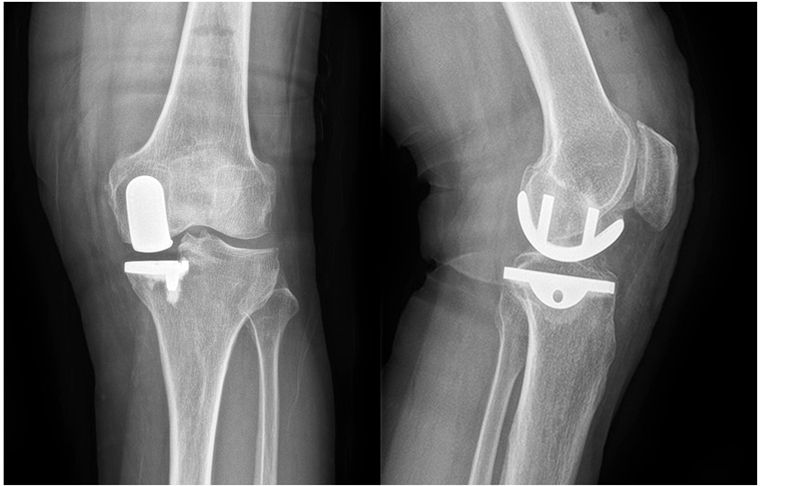

(1)70岁女性患者,以左膝关节疼痛5年、加重1年为主诉入院,入院查体左下肢内翻畸形11°,膝关节内侧间隙压痛阳性,外侧无压痛,髌骨研磨试验阴性,抽屉试验阴性,ROM 5°~120°,诊断左膝关节前内侧骨关节炎,行左膝关节内侧固定平台单髁置换术。术后给予预防感染、消肿止痛及抗凝治疗,术后24h康复师指导助行器辅助下床活动,术后1个月膝关节 HSS评分由63分升至85分,KSS评分由49分升至80分,内侧疼痛消失,患者恢复满意。手术前后影像学资料见图1~2。

图2术后 X线片示假体位置良好,大小合适